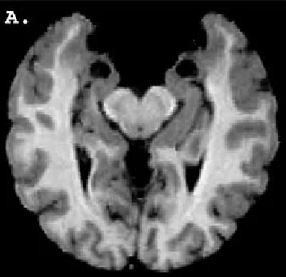

Amerika'nın Kentucky eyaletinde yaşayan bir kadın, beyninin Amigala kısmında yer alan genetik bir bozukluk nedeniyle korku duygusuna sahip değil.

İlk olarak 1994 yılında tıp literatürüne giren bu rahatsızlığın genel ismi Urbach-Wiethe.